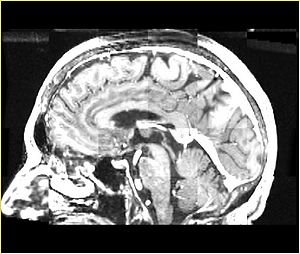

• Checkerboard appearance of unregistered images for the representative data of interest

• Case03